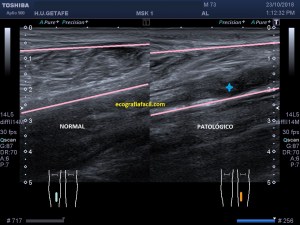

Con la eco pasa igual…cuando queremos estudiar, por ejemplo, el recto anterior del muslo en axial,perfecto…pero en longitudinal, como la imagen 2, se complica porque desde la rótula a la inserción en la cadera, tenemos mucho recorrido. En este caso hacemos lo mismo que cuando hacemos la foto del atardecer…nos ponemos en un extremo, activamos la funciona, recorremos suave y continuamente por la anatomía que queremos fotografiar y ya está…mira la pantalla y no el movimiento de tu mano,como si hicieses la foto, ves la pantalla,pero no como mueves el teléfono.

Es muy útil para lesiones que han crecido mucho y no podemos conjugar en una sola imagen, por ejemplo, un lipoma, cuando superan la medida de la huella de la sonda no son medibles, hay que usar «panoramic view», y como este caso, otros muchos.

En la imagen 3 ves una imagen de un lipoma, mide 7 cms, la huella de la sonda mide 5cms, la «panoramic view» posee una regla centimetrada que sigue el contorno de la imagen, justo en la profundidad de la misma y lo marca la flecha amarilla. La profundidad la marca la flecha roja y la flecha blanca marca el rango centimetral de los 5cms, fíjate que la línea blanca es ligeramente mayor cada 5 cms. Sirve de referencia, como en la imagen 4 donde ves una colección en el glúteo de más de 10 cms.